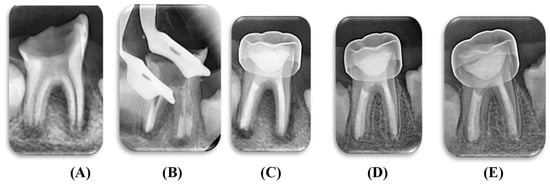

2.7. Clinical Procedures

2.8. Biomechanical Preparation

2.9. Filling of the Root Canals

2.10. Coronal Restoration